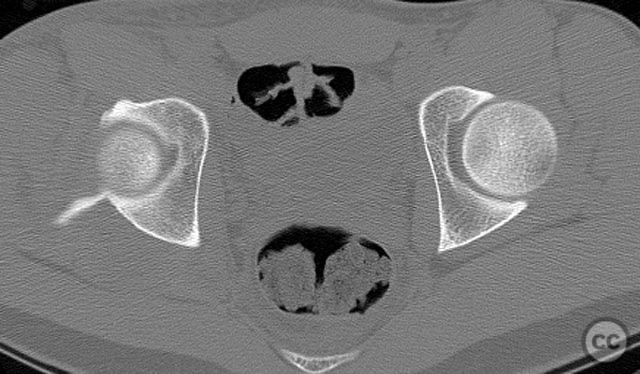

Clinical and radiological findings:  A 20-year-old male collegiate basketball player sustained a displaced right posterior wall (PW) acetabular fracture-dislocation during practice. Initial AP pelvic radiograph demonstrated a reduced femoral head with a displaced posterior wall fragment. Axial CT imaging revealed a large, peripherally located PW fragment with significant displacement, impaction into the abductor muscle mass, and no intra-articular comminution. Obturator oblique radiographs and intraoperative fluoroscopy under anesthesia demonstrated mechanical obstruction to passive abduction at 10–20 degrees due to the relationship between the displaced PW fragment and the greater trochanter.

Intraoperatively, the posterior wall fragment was found firmly embedded within the abductor musculature, necessitating careful disimpaction and minimal periosteal stripping to preserve vascularity. The spring-hook device provided secure capture of the peripheral fragment without involving the labrum. Placement of the reconstruction plate medial to the hook tines provided buttress support to prevent secondary displacement. Fluoroscopic imaging confirmed anatomic reduction and extra-articular screw placement. Postoperative CT demonstrated satisfactory reduction and implant positioning.